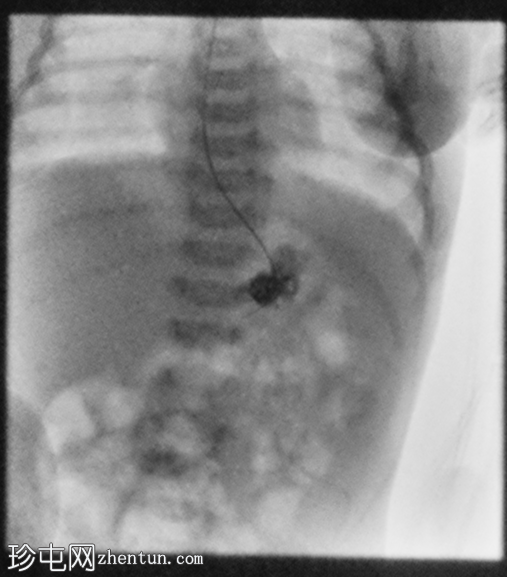

足月新生儿无法耐受任何喂养,经胃管/口服喂养后出现大量呕吐。评估是否存在肠旋转不良和胃排空障碍。

胃部初始显影,并立即反流至食管裂孔疝。在其近端可见管径正常的远端食管。十二指肠降部和横部显影较弱,左上腹可见数段管径较小/部分减压的近端小肠显影。

延迟1小时拍摄的X线片显示食管裂孔疝和胃部仍有造影剂残留,造影剂远端扩散受限,很可能是由于造影剂用量较少所致。充满气体的肠袢外观正常,乙状结肠内可见气体,直肠内未见气体。

这是一例儿童患者在透视下发现的食管裂孔疝病例。

最初的临床考虑是肠旋转不良,因为患者频繁且呕吐量大,但后来怀疑这是由中等大小的食管裂孔疝引起的。